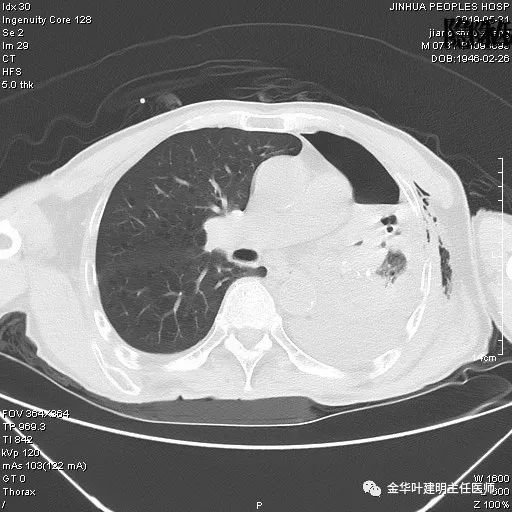

考虑左侧大量胸腔积液,遂进一步胸部CT检查:

以上是肺窗表现,下面为纵隔窗影像: